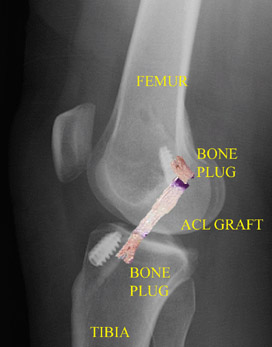

Post-operative X-ray after ACL patellar tendon reconstruction (with picture of graft superimposed) shows graft position and bone plugs fixation with metal interference screws.